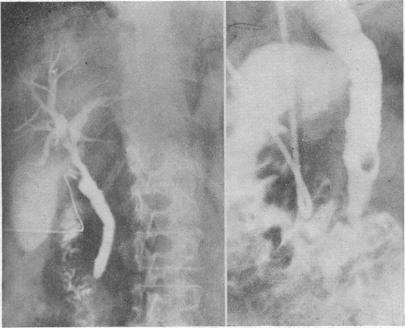

Contract cholangiography.

Clinical, operative, and conventional radiological criteria may provide insufficient indications for exploration of the common bile duct. The technique of contact cholangiography improves the radiographic definition, especially in the obese, and has resulted in more positive choledochotomies and in fewer negative explorations.